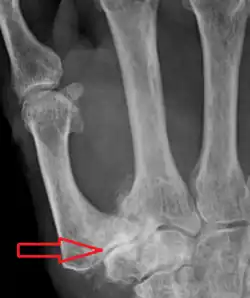

| Osteoarthritis of the trapeziometacarpal joint | |

Trapeziometacarpal osteoarthritis (TMC OA) is, also known as osteoarthritis at the base of the thumb, thumb carpometacarpal osteoarthritis, basilar (or basal) joint arthritis, or as rhizarthrosis.[3][1][2] This joint is formed by the trapezium bone of the wrist and the metacarpal bone of the thumb. This is one of the joints where most humans develop osteoarthritis with age.[4] Osteoarthritis is age-related loss of the smooth surface of the bone where it moves against another bone (cartilage of the joint).[3][5] In reaction to the loss of cartilage, the bones thicken at the joint surface, resulting in subchondral sclerosis. Also, bony outgrowths, called osteophytes (also known as "bone spurs"), are formed at the joint margins.[6]

TMC OA is diagnosed based on symptoms and signs.[8] Radiographs can confirm the diagnosis and the severity of TMC OA. Other diagnoses in this region include scaphotrapezial trapezoid arthritis and first dorsal compartment tendinopathy (De Quervain syndrome) although these are usually easy to distinguish.

TMC OA severity was classified by Eaton and Littler which can be simplified as follows:[21][22]

Stage 1:

- slight widening of the joint space

- < 1/3 subluxation of the joint (in any projection)

Stage 2:

- Osteophytes, < 2 mm in diameter, are present. (usually adjacent to the volar or dorsal facets of the trapezium)

Stage 3:

- Osteophytes, > 2 mm in diameter, are present (usually adjacent to the volar and dorsal facets of the trapezium)

- Slight joint space narrowing

Stage 4:

- Narrow joint space

- Concomitant scaphotrapezial arthritis

A simpler classification is no arthritis, some arthritis, and severe arthritis.[23] This simpler classification system omits the potentially contradictory details of the Eaton/Littler classification and keeps scaphotrapezial arthrosis separate.